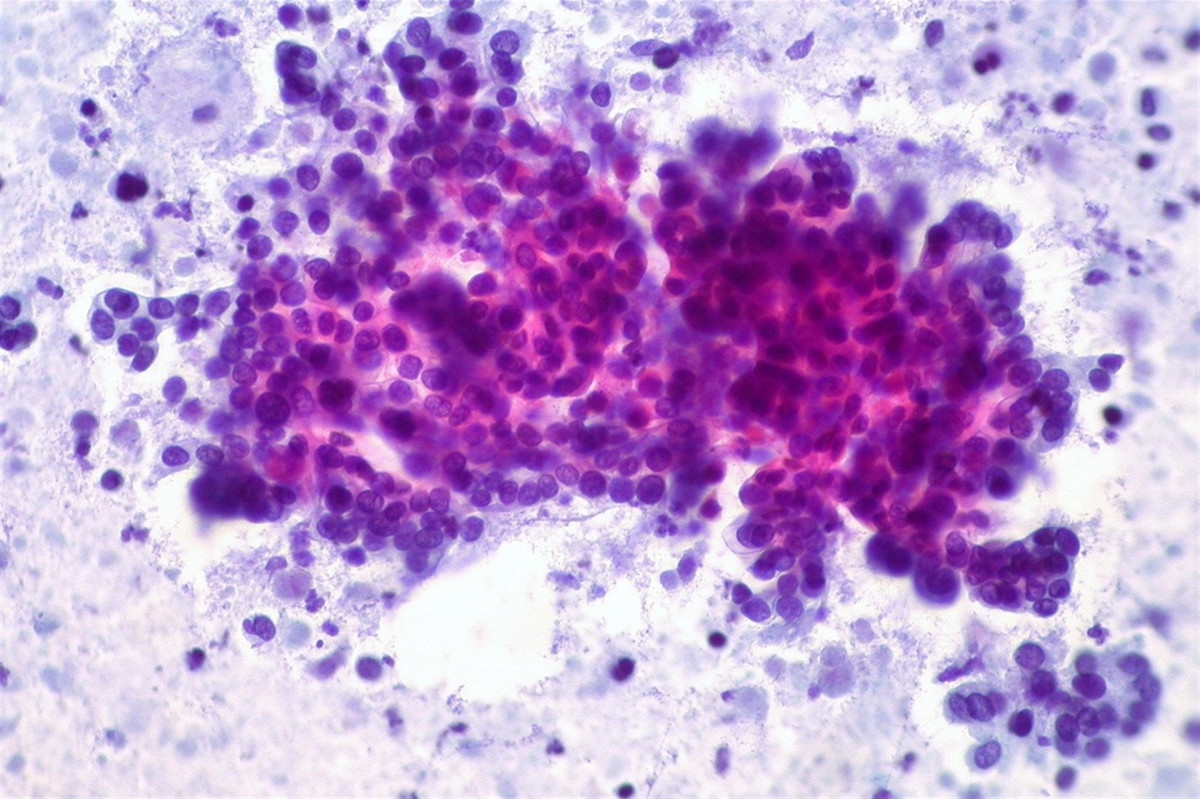

Cáncer de páncreas